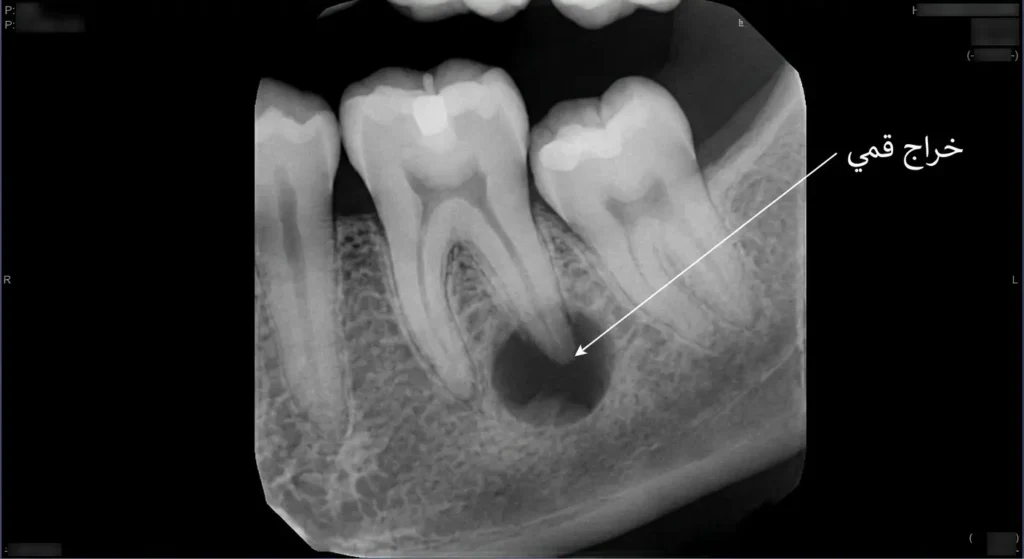

الخراج القمي (Periapical Abscess)

هذا النوع هو الأكثر انتشاراً. يتشكل في قمة جذر السن (Apex)، أي في أعمق نقطة تحت اللثة. السبب الرئيس له هو التسوس العميق الذي وصل إلى لب السن وأمات العصب. البكتيريا تنتقل عبر القنوات الجذرية (Root Canals) لتخرج من فتحة الجذر وتصيب العظم المحيط. المريض في هذه الحالة يشعر بألم عند العض على السن المصاب، وأحياناً يظهر انتفاخ صغير على اللثة يشبه البثرة يسمى الناسور (Fistula أو Sinus Tract).

الأشعة السينية (X-rays) لا غنى عنها. في الأشعة حول الذروية (Periapical Radiograph)، يظهر الخراج القمي كمنطقة داكنة (Radiolucent) حول قمة الجذر، مما يعني تآكلاً في العظم نتيجة العدوى. هذه الصورة الشعاعية تكشف أيضاً عمق التسوس وحالة علاج عصب سابق إن وُجد. في بعض الحالات المعقدة يلجأ الطبيب إلى الأشعة المقطعية المخروطية (CBCT – Cone Beam Computed Tomography) التي تعطي صورة ثلاثية الأبعاد دقيقة جداً لموقع الخراج وحجمه وعلاقته بالهياكل التشريحية المجاورة.

أحياناً يظهر الخراج في الأشعة السينية بوضوح بينما لا يشعر المريض بأي ألم. هذا يحدث عندما يكون الخراج مزمناً (Chronic Abscess) ويتصرف ببطء عبر ناسور، فيُفرّغ الضغط تلقائياً. غياب الألم لا يعني غياب الخطر — فالعدوى المزمنة تُدمر العظم المحيط بصمت.